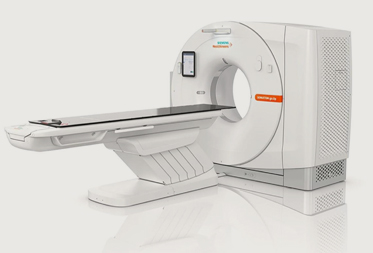

With a focus on early detection and preventive care, our health checkups are designed to provide a complete assessment of your overall wellness. From basic screening to advanced diagnostics, we use state-of-the-art equipment and trusted medical protocols to ensure high-quality results you can rely on.

Our team of skilled pathologists, radiologists, and support staff work with care and precision, making your health our top priority. Whether you need a routine checkup, full-body screening, or specialized tests, Unicare is your one-stop destination for dependable diagnostics.